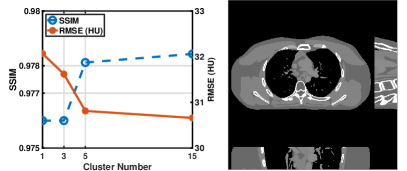

We evaluate the behavior of the PWLS-ULTRA method (with ) for 3D cone-beam CT data with . Fig.Β 2 shows the central slices along three directions for the underlying (true) XCAT phantom volume. We reconstruct the volume from low-dose CT measurements. Fig.Β 2 shows the RMSE and SSIM of PWLS-ULTRA for various choices of , the number of clusters (patch size and patch stride ). Rich models (large ) produce better reconstructions compared to using a single ST (). For the piece-wise constant phantom, clusters works well enough, with only a small additional RMSE or SSIM improvement observed for larger . Larger values of led to sharper image edges.